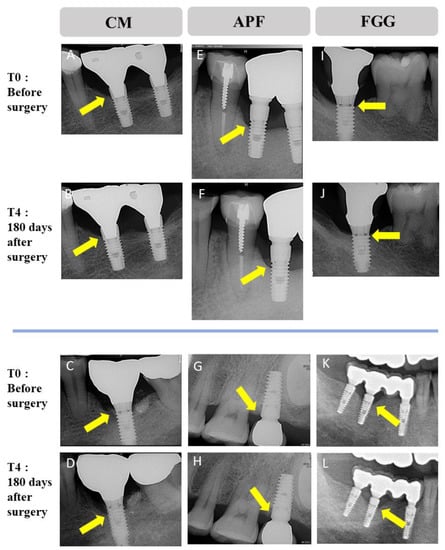

3.5. Bone-Level Change around Implant